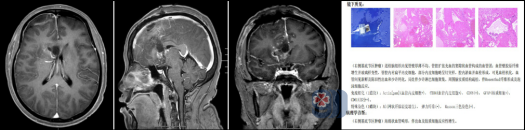

入院后,神经外十科团队为凌某完善了高磁场、高分辨率头颅MR及SWI序列检查。结果清晰显示:右侧基底节区、放射冠多发病变,较大者约25mm×22mm,明确诊断为“海绵状血管畸形”,并合并发育性静脉异常。

面对挑战,神经外十科团队组织了多次术前讨论,制定了精细化的手术入路与应急预案。在征得患者及家属充分知情同意后,在欧阳辉教授和林德留主任的带领下,在神经导航与高精度显微镜辅助下,右侧纵裂入路,手术历时5小时,于毫厘之间完整切除病灶,术中成功避开了周围重要的神经传导束与大脑前动脉。

术后凌某恢复顺利,复查头颅MR显示病灶全切,无残留。术后病理证实为“海绵状血管畸形,伴出血及胶质细胞反应性增生”。出院时,凌某神志清醒,语言流利,四肢活动自如,未出现任何新增神经功能缺损。

海绵状血管畸形(以前称海绵状血管瘤)并非真性肿瘤,而是一种先天性脑血管发育异常。其血管壁缺乏弹力层与肌层,结构脆弱,如同一团“桑葚”状的不规则血管团,极易反复发生微量或显性出血。